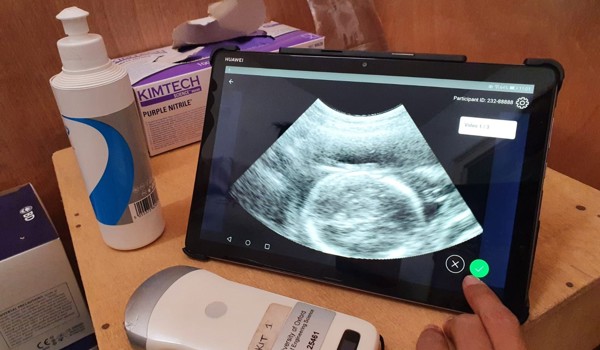

A particular focus for the group has been understanding the interplay of ultrasound device design (physics), clinical acquisition, and downstream image analysis and computer vision. Much of our recent work has concerned machine learning in ultrasound. We are interested in answering questions such as why is ultrasound scanning and interpretation hard to learn? How can we get computers to mimic what a skilled sonographer can do? What is the role of multi-modal analysis (such as eye-tracking and ultrasound video) in ultrasound imaging? And can ultrasound be simplified (assisted by AI-assistive technologies) so that minimally trained clinical professionals can use it in non-traditional healthcare settings. Our research is motivated by unmet important clinical needs in developed world and developing world settings and involves inter-disciplinary translational research collaborations with clinical groups from the UK and overseas.